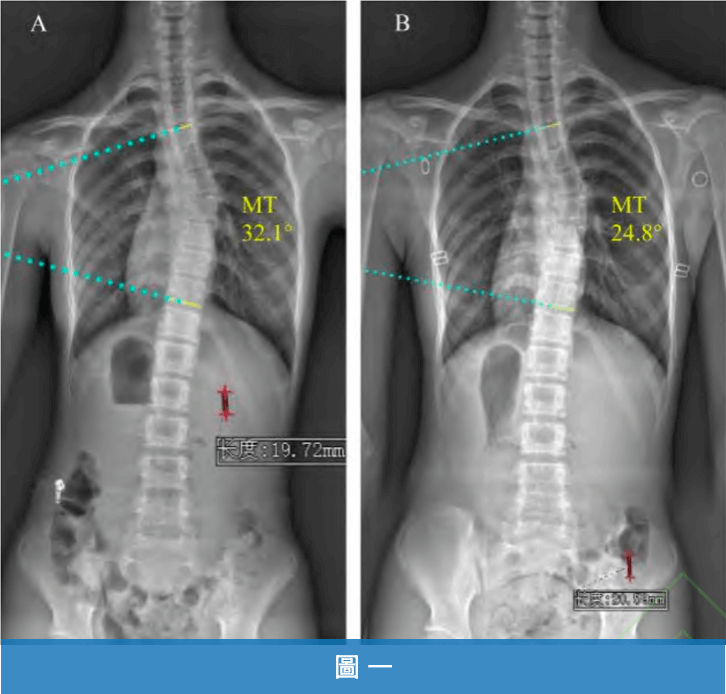

側彎度數在矯正完成3個月後進行評估,度數由29.14°±9.28° 降至22.69°±9.23(圖一),顯示矯正成效具有持續性。

《圖一》大腦學習訓練法21天密集訓練成功改善側彎度數 A:治療前主胸彎為 32.1°;B:3個月後主胸彎降至 24.8°。顯示側彎矯正成效至少持續3個月。